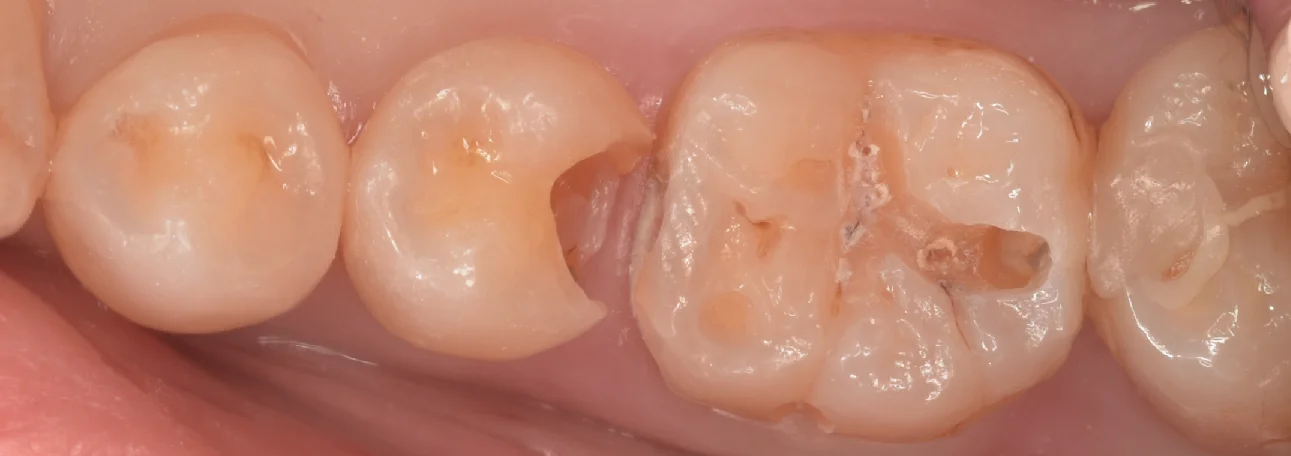

まずは術前からです。

上が真上からのアングル・下が側面からのアングルで撮影を行なっています。

というのも、この歯ですが、上下左右全ての面に継ぎ接ぎ状に治療がされており、その接合部分から内部に虫歯ができているような状態だったんです。

なので側面からも併せて撮ることで状況がよりわかりやすくなりそうだったので今回はそういう方向で撮影することにしました。